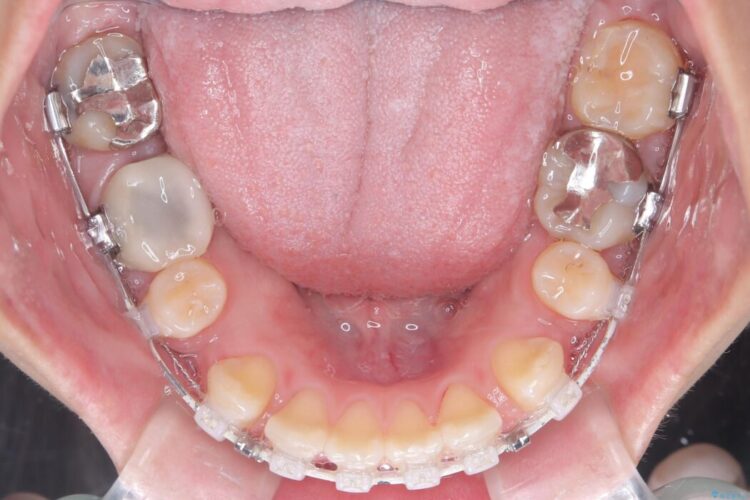

- 矯正装置:ハーフリンガル矯正

装置は人目を気にせず治療できるよう、上顎に裏側矯正、下顎に表側矯正を組み合わせたハーフリンガル矯正を提案しました。

装置には、上顎には目立たない裏側矯正(舌側矯正)を、下顎には透明な審美ブラケットを使用するハーフリンガル矯正を採用しました。抜歯によってできたスペースを最大限に活用し、前歯を効率よく後方へ移動。治療の結果、口元の突出感が大幅に解消され、Eライン(横顔の美しさの基準)も改善しました。人目を気にすることなく治療を完遂し、自信の持てる美しい横顔を獲得していただけました。